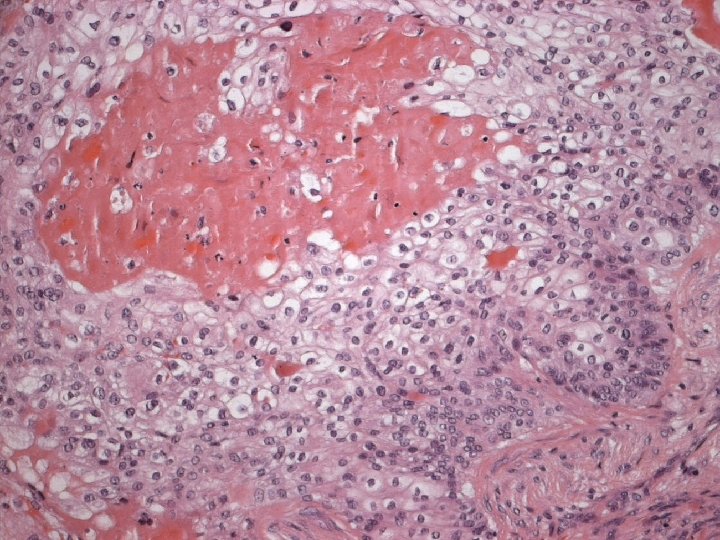

Micro n Similar to SCC at other sites n Cytoplasmic clearing in some

Micro The strongest evidence of a primary SCC of breast is presence of in-situ squamous carcinoma in duct or cyst lining.

Micro n Exclude metastasis – Most common sites: lung, uterine cervix, urinary bladder. – Cystic degeneration NOT seen in metastatic carcinoma